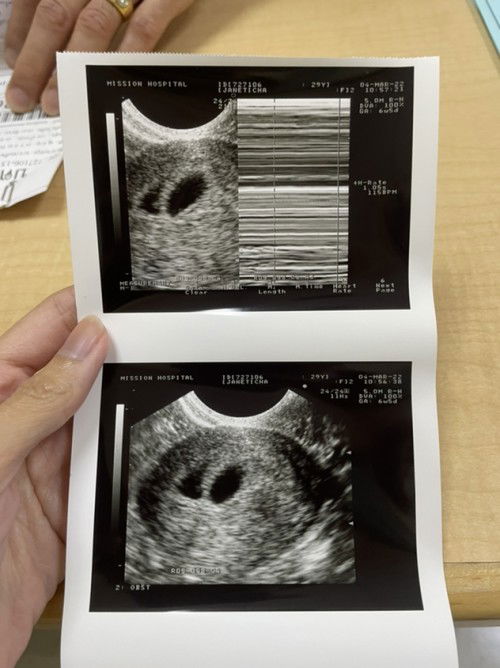

วันนี้เราไปอัลตราซาวด์มาเจอถุงตั้งครรภ์ 2 ใบ ถุง 1 ใบมีหัวใจเต้นแล้วแต่ถุงอีก 1 ใบ คุณหมอบอกว่ารอลุ้นเพราะหัวใจอาจจะมาช้ากว่า ถ้าไม่มีเขาจะฝ่อไป มีแม่ๆคนไหนบ้างที่เจอเคสแบบนี้บ้างคะ